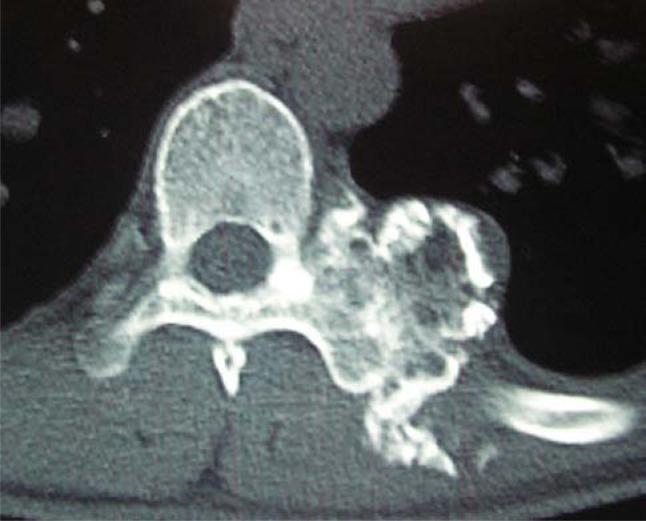

The incidence of osteochondroma is rare and only 2% of such tumors are found in the spine area. When they are found in the vertebral column, less than 1% of all osteochondromas and few tumors occur in the thoracic vertebrae. An osteochondroma arising from the transverse process of the vertebra is even rarer, especially following from the thoracic transverse process. Here we report a giant solitary osteochondroma arising from the thoracic transverse process of T8 vertebra and involving the corresponding transverse process and rib. A 28-year-old man presented with a progressive thoracic node, and neuroradiological evaluation of the spine showed a giant mass lesion involving the transverse process of T8 vertebra and concomitant corresponding facet joint and rib on the left side. At surgery, a firm and cartilaginous tumor originating from the transverse process was radically excised and surgical curettage of the lesion was performed. It is concluded that accurate and prompt diagnosis requires a high index of suspicion followed by surgical treatment to prevent severe morbidity in cases of primary spinal column tumors. The histological examination of this patient revealed the lesion was osteochondroma. The best choice of treatment for spinal osteochondromas is surgical excision or curettage and spinal stabilization, if necessary.